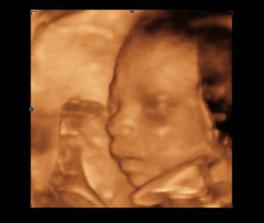

14.1.2010 3D ultrazvuk podľa PM presne 13tt+0 , na drobčeka sa bol pozrieť 1.krat aj tatinko, bolo to krásne 🙂 /////